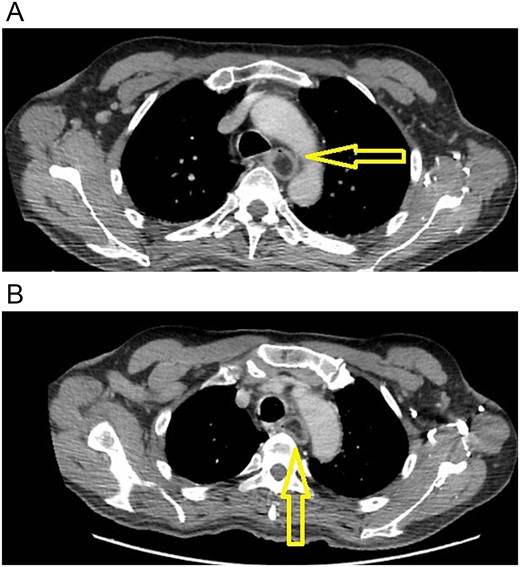

The patient is a 70-year-old male with a past medical history of prostate cancer. He presented with a two-year history of progressive dysphagia. At first, he complained of epigastric pain, nausea, and vomits. In the last three months, he found it increasingly difficult to eat anything solid, until he found it impossible to swallow. Due to this, an upper endoscopy and a contrast-enhanced chest computed tomography (CT) were done at that time, revealing a giant superior esophageal polyp (Fig. 1) 28 cm away from the dental arcade; therefore, surgical resection was recommended. Nonetheless, the patient refused any surgical management.

(A) CT scan: esophageal polyp is seen in the esophageal lumen. (B) CT scan: esophageal polyp completely obstructs but does not invade the esophagus.